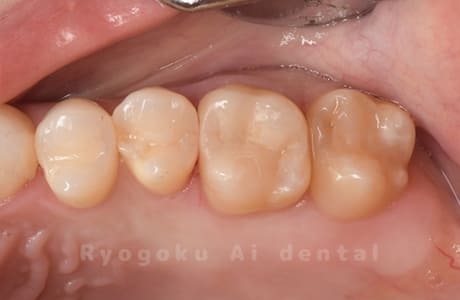

Case08

-

- 原因

- 虫歯

- 治療内容

- セラミックインレー

- 治療費用

- 77,000円

奥歯の黒い点が気になるということで来院された患者さんです。白い詰め物を外したところ、虫歯が中で大きく広がっていたため、患者さんと相談し、セラミックインレーで治療を行いました。

<リスク・副作用>

過度の咬合や衝撃で割れることがあります。